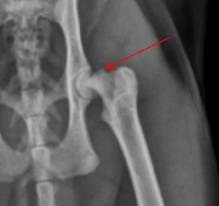

2 years old male castrated cat

Severe sudden onset lameness of pelvic limb

Displaced capital physeal fracture of the left femoral head with mild cranial displacement of the femoral neck. On the frog-legged VD projections, this displacement is not visualizing so well.

Most of the physes of the pelvic limbs are at least partially open, including the intact right femoral capital physis (castrated young).

Diagnosis: Left sided capital physeal fracture of the left pelvic limb and delayed physeal closure in both hind limbs.